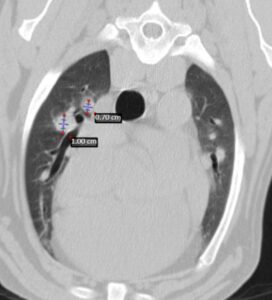

A los 18 meses del diagnóstico, los cuidadores refieren la aparición de hifema y exoftalmia en el ojo derecho, lo que sugiere metástasis, además de una masa perianal compatible con neoplasia indiferenciada (posible melanoma amelanótico). En el estudio de TC se documenta una respuesta completa de la lesión primaria y metástasis nodales y una remisión casi completa de las metástasis pulmonares (lesiones milimétricas equívocas) (imagen 1). Se realiza la resección de la masa perianal, pero los cuidadores rechazan la enucleación.

A los 28 meses se realiza un TC de re-estadiaje antes de considerar el segundo protocolo de radioterapia, donde se documenta una progresión objetiva de la masa oral y ligera progresión de la metástasis pulmonar (imagen 1).